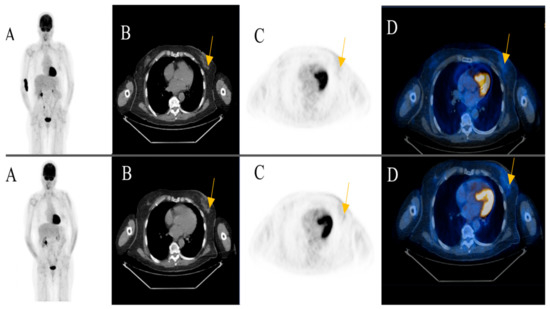

Among the patients with additional primary cancers, an indeterminate subcutaneous nodule was seen in the left breast of an 81-year-old female patient in post treatment surveillance (initially with metastatic cutaneous melanoma stage IV). The reporting physicians recommended an ultrasound-guided biopsy for further evaluation. The biopsy revealed an invasive ductal breast cancer (Figure 3) (Case 1).

Figure 3. An 81-year-old female patient initially with metastatic cutaneous melanoma stage IV (pT2a N3 M1b). (A) Maximum intensity projection (MIP); (B) Computed Tomography (CT) axial of chest; (C) Positron Emission Tomography( PET) axial of chest; (D) Fused images PET/CT axial of chest. First row: FDG-PET/CT performed for surveillance after treatment without evidence of metabolically active recurrence, nodal or distant metastasis. Contamination at injection site cubital on the right upper extremity. Second row: Six months later, a morphologic and metabolic progredient subcutaneous nodule in the left breast was seen (yellow arrow). An ultrasound-guided biopsy was subsequently recommended for further evaluation. The biopsy revealed an invasive ductal breast cancer.